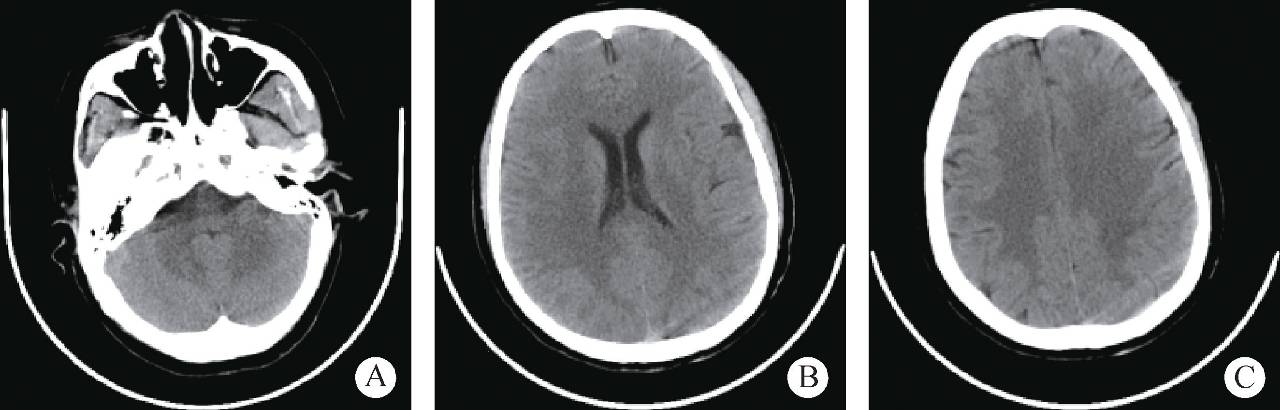

患者女性,36岁,经阴道自然分娩2天后,突发喷射样呕吐,伴有头晕、视物不清及意识障碍,随后出现胡言乱语、答非所问。发病3小时后出现呼之不应、牙关紧闭、四肢乱动、双眼直视、伴舌咬伤,入院后查体见球结膜出血水肿,颜面部出血伴皮下出血点,对光反射迟钝,疼痛刺激反应正常,无其他阳性体征,监测生命体征,完善各项影像学检查均未见明显异常(图1、图2)。

图1 发病第2天头颅CT(未见明显异常)